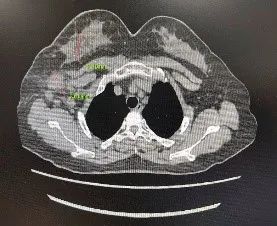

▌影像学评估(CT):

图4. 基线与6周期治疗后CT影像

该患者分别于2021-10-15、2021-11-5、2021-12-1、2021-12-22、2022-1-13、2022-2-8完成6周期新辅助化疗,方案:TCbHP,紫杉醇脂质体210mg+卡铂 0.6g+汉曲优(首次剂量 500mg,维持剂量380mg)+帕妥珠单抗(首次剂量 840mg,维持剂量420mg),该患者在完成第一周期新辅助化疗后,自觉肿块明显缩小,在行第3周期新辅助化疗入院后,予以完善乳腺MRI提示,乳腺肿物及腋窝淋巴结均明显缩小,查体几乎无法触及乳腺肿物及腋窝肿大淋巴结,继续完成6周期足量新辅助化疗后行乳腺癌改良根治术。